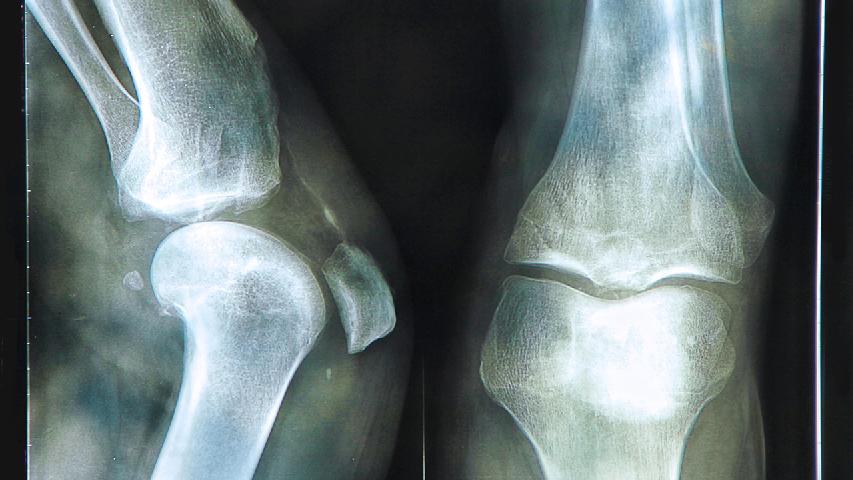

2、关节肿痛:多呈对称性,常侵及掌指关节、腕关节、肩关节、趾间关节、踝关节及膝关节。关节红、肿、热、痛、活动障碍。

3、畸形:后期病例一般均出现掌指关节屈曲及尺偏畸形;如发生在足趾,则呈现爪状趾畸形外观。